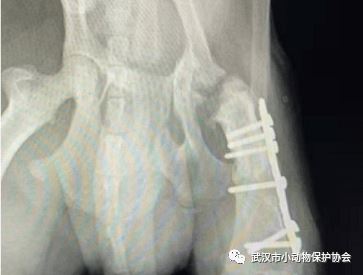

救助地点:竹叶山

救助故事:微信的网友求助,在汉口竹叶山天桥下发现一只受伤阿拉斯加不能动,他先安置在门面,第二天送到了协会帮忙联系好的医院,狗狗的X光显示小腿有一处骨折,静养几天后,为它安排骨科手术。住院两周后安排出院,现在已经被领养。

小竹子的手术和住院费用是3600元。